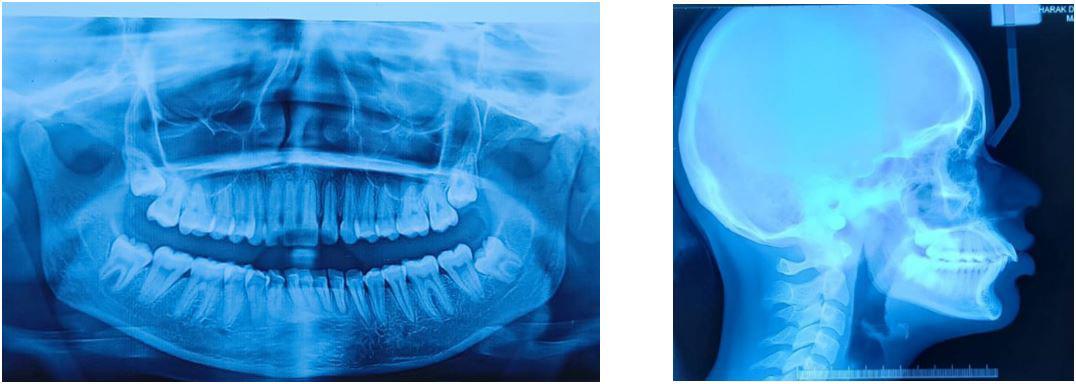

Pre-treatment (T0) and post-treatment (T1) profile photographs were collected from the treating orthodontist and pre-treatment (T0) and post-treatment (T1) selfies were collected after verbal and written informed consent from the patient. Data was collected from departments of orthodontics from various dental colleges across India.

Keeping type I error=5 % and power of the study at 80%, sample size was estimated to be 24 subjects in each group. Subjects were classified according to their ANB angle values provided by their orthodontists into Skeletal Class I (SCI), Skeletal Class II (SCII), and Skeletal Class III (SCIII). Each skeletal class group had 12 male and 12 female subjects. Three panels were constituted consisting of 3 orthodontists (O), 3 general dentists (GD), 3 lay persons (LP).

All selfies at T0 and T1 were cropped up to the clavicle of the subject if visible. The backgrounds of the selfies were removed and turned white with the help of Adobe Photoshop CC 2020 version 21.1 software package (Adobe Systems, San Jose, CA). One example of pre-treatment and post-treatment selfies of a subject in skeletal class I is illustrated in Figure 1A and 1B, in skeletal

Figure 1: Skeletal Class I Group (SCI) Male.

A-Pre-treatment (T0) Selfie; B- Post-treatment (T1) Selfie; C. Pretreatment Profile Silhouette (T0). D. Post-treatment Profile Silhouette

Figure 2: Skeletal Class II Group (SCII) Female.

A-Pre-treatment Selfie (T0), B- Post-treatment Selfie (T1). C. Pretreatment Profile Silhouette (T0), D. Post-treatment Profile Silhouette (T1).

Figure 3: Skeletal Class II Group (SCII) Female.

class II is illustrated in Figure 2A and 2B, and in skeletal class III is illustrated in Figures 3A and 3B.

All profile photographs at T0 and T1 were cropped up to the clavicle of the subject. Profile photographs were converted into black silhouettes against a white background using Adobe Photoshop CC 2020 version 21.1 software package (Adobe Systems, San Jose, CA) One example of pre-treatment and posttreatment profile silhouettes of a subject in skeletal class I is illustrated in Figure 1C and 1D, in skeletal class II is illustrated in Figure 2C and 2D, and in skeletal class III is illustrated in Figure 3C and 3D.